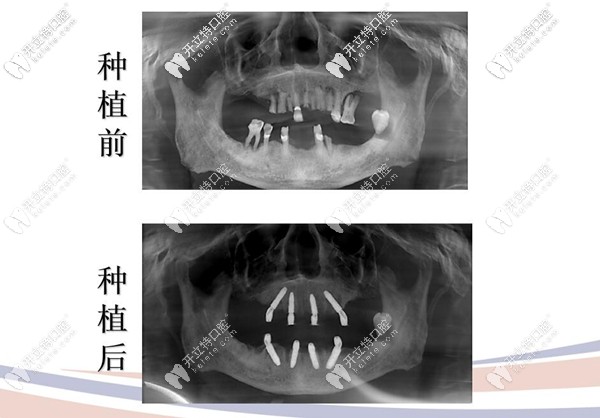

種植牙前后拍片圖示

治療方案:拔除松動(dòng)牙,采用極光美式定制植牙All-on-4技術(shù),即刻種植,即刻修復(fù)當(dāng)天就能用哦!

顧客反饋:原來(lái)上下牙各用4顆種植體就可以恢復(fù)全口牙齒的咀嚼功能呀,這簡(jiǎn)直有點(diǎn)神奇,當(dāng)天就可以吃東西,真的是錢花哪哪舒服啊,“我”也挺滿意的。